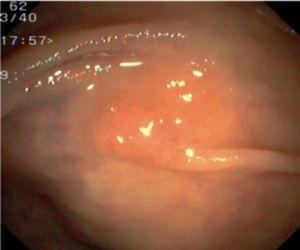

Fig. 3. Examples of flat lesions with conventional examination and after the application of indigo carmine 0.2-0.5%. a, b) Small flat adenoma, 3 mm in size. c, d) Large flat adenoma, 15 mm in size. e, f) Completely flat lesion (IIb in the Japanese classification). g, h) Depressed lesion, 3 mm in size) (IIc in the Japanese classification). I, J) Depressed lesion, 7 mm in size, histopathological study revealed submucosally invasive cancer (traditionally IIc in the Japanese classification, although recently such depressed lesions with a distinct central protrusion indicating submucosal invasion are termed IIc + Is). k, l) Flat elevated lesion with central depression, 10 mm in size, corresponding to a submucosally invasive cancer (IIa + IIc in the Japanese classification).